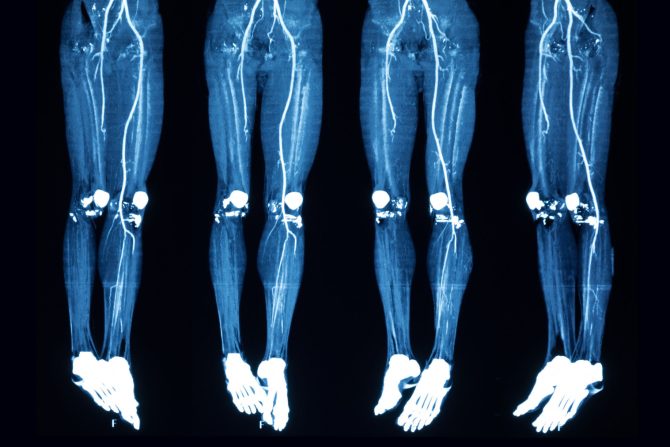

Dijagnostika je jednostavna i uključuje sledeće metode: tzv. test provocirane hiperemije, dopler sonografiju, arteriografiju i MSCT-arteriografiju (multislajsna kompjuterizovana tomografija).